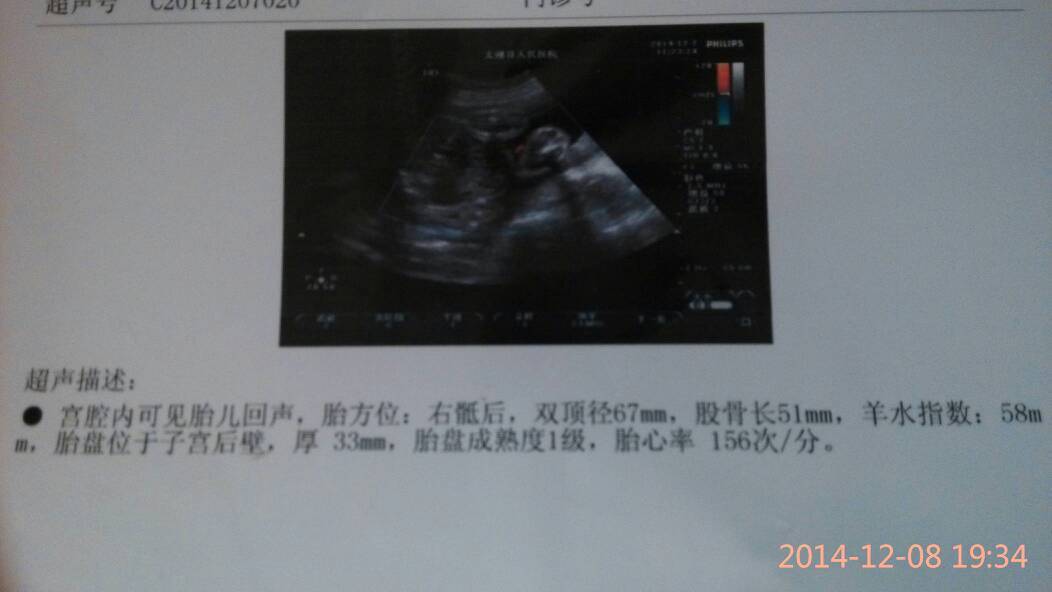

你好,看报告胎儿的胎心率正常,但是羊水是不是会偏少了呢,羊水指数的正常值是在8---20cm之间的,你的报告提示羊水指数是58mm是偏少的,如果测量的是羊水深度的话,在3---8cm之间是正常范围的,建议复查确定羊水情况,